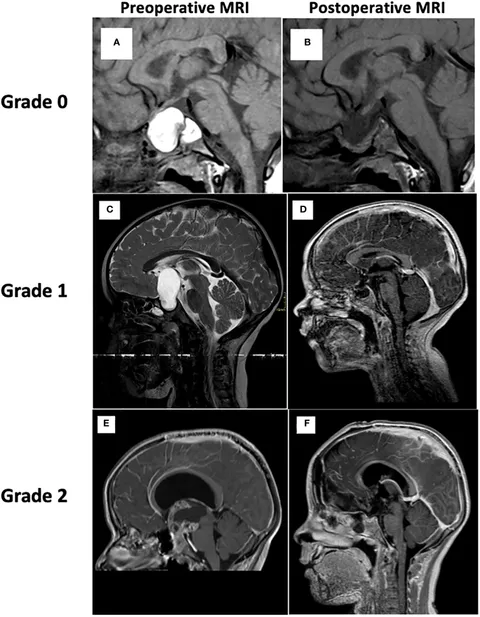

小児神経の画像診断 改訂第2版: ―脳脊髄から頭頸部・骨軟部まで。Neuroimaging Findings in a Patient with Anti-IgLON5 Disease。Topography and Radiological Variables as Ancillary。「小児神経の画像診断 = Diagnostic Imaging of Infantile Neurologic Diseases : 脳脊髄から頭頸部・骨軟部まで」大場 洋 / 大場 洋 / 髙梨 潤一 / 髙梨 潤一 / 森 墾 / 森 墾定価: ¥ 15000裁断しています。タイ方医学知識と理論。#大場洋 #大場_洋 #大場洋 #大場_洋 #髙梨潤一 #髙梨_潤一 #髙梨潤一 #髙梨_潤一 #森墾 #森_墾 #森墾 #森_墾 #本 #自然/医療・薬学・健康。健康教育マニュアル。書き込み等はありません。ページも全て揃ってページ順となってます。病理解剖実践ガイドブック 2025